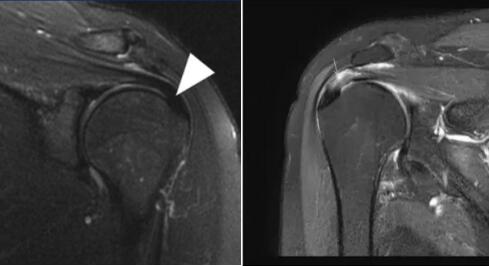

正常肩袖核磁共振圖像 ???肩峰撞擊后導(dǎo)致肩袖上表面撕裂

“患了肩峰撞擊綜合征,通常只要適量運(yùn)動(dòng),經(jīng)過充分休息是不會(huì)發(fā)生肩痛的。但是有一類人群應(yīng)當(dāng)注意,那就是三型肩峰。”李彬主任進(jìn)一步說到,肩峰撞擊綜合征分為三種類型,一型為平坦型,在肩關(guān)節(jié)外展活動(dòng)時(shí)發(fā)生撞擊或撞擊的程度較輕;二型為肩峰弧形,在肩關(guān)節(jié)外展活動(dòng)時(shí)發(fā)生撞擊或撞擊的程度較一型要重,多為40歲以上中老年患者;三型肩峰為鉤型肩峰,在肩關(guān)節(jié)外展活動(dòng)時(shí)發(fā)生撞擊或撞擊的程度較高。89%的三型肩峰存在肩峰撞擊,撞擊后容易造成肩峰下肩袖肌腱撕裂。

但是,病情為三型肩峰撞擊綜合征伴肩袖損傷病患者,則需要通過肩關(guān)節(jié)鏡手術(shù)進(jìn)行治療。大多數(shù)患者因?yàn)椴涣私饧珀P(guān)節(jié)手術(shù),所以有點(diǎn)排斥或不愿意接受手術(shù)治療。